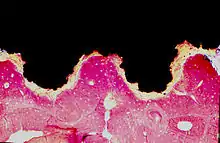

Titanium implant (black) integrated into bone (red): Histologic section